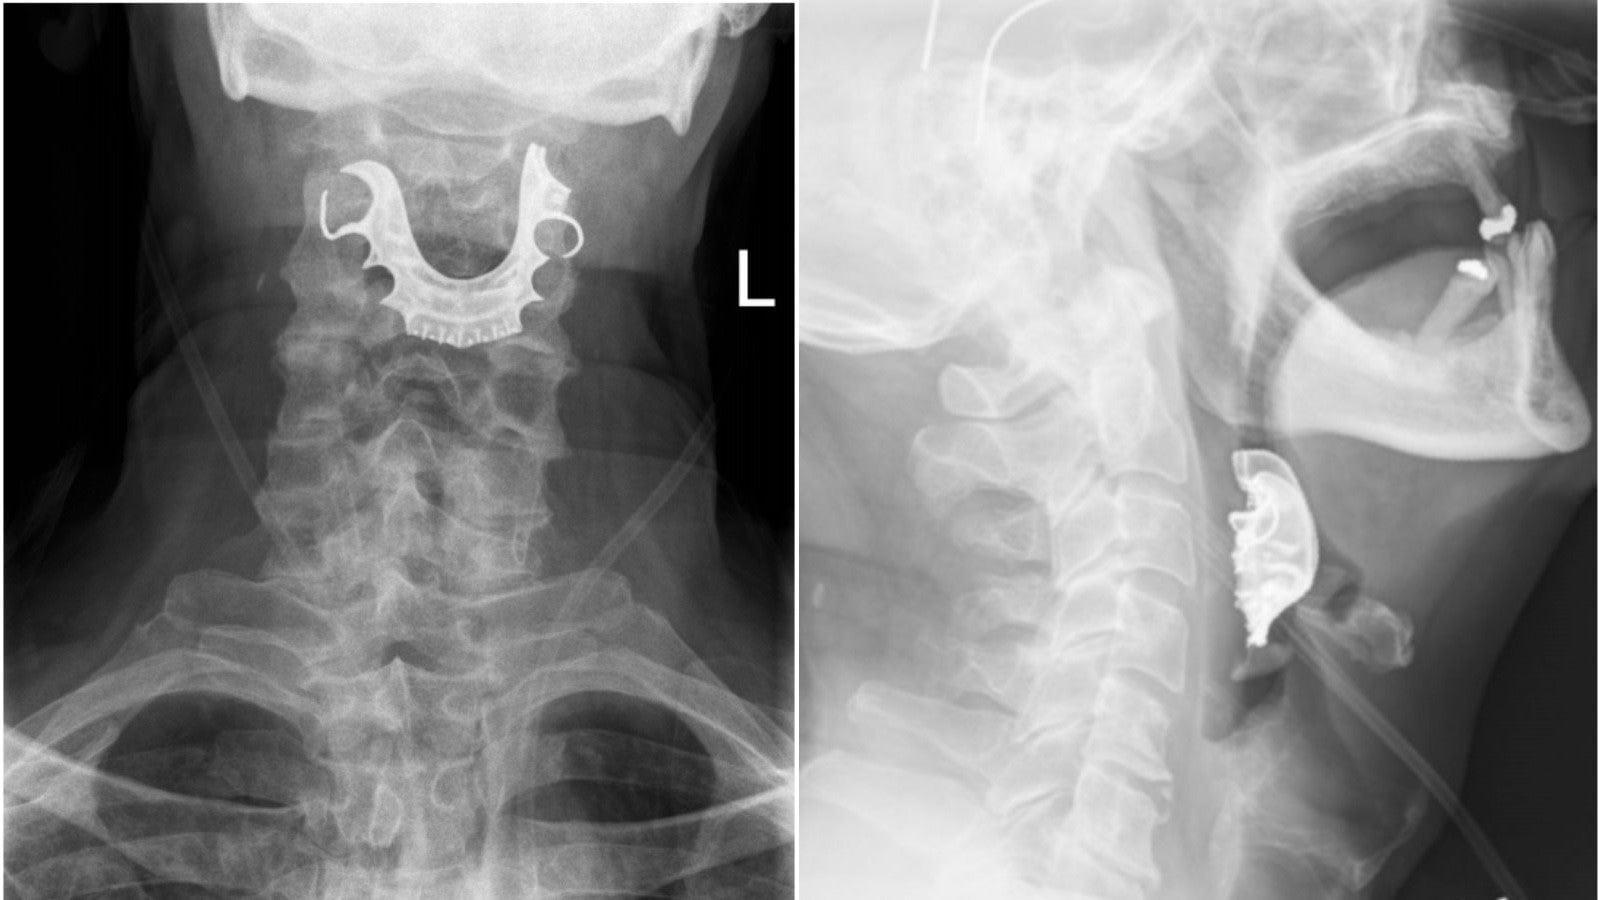

But when a new set of doctors actually looked inside the man’s throat, after the man again complained about his symptoms, they quickly spotted something lodged across his larynx. And that’s when the man revealed that his partial dentures had mysteriously gotten lost about a week earlier. The most likely scenario is that the man had inhaled them when he was intubated.

Though doctors soon removed the clandestine throat teeth with forceps, the man’s suffering wasn’t over yet.